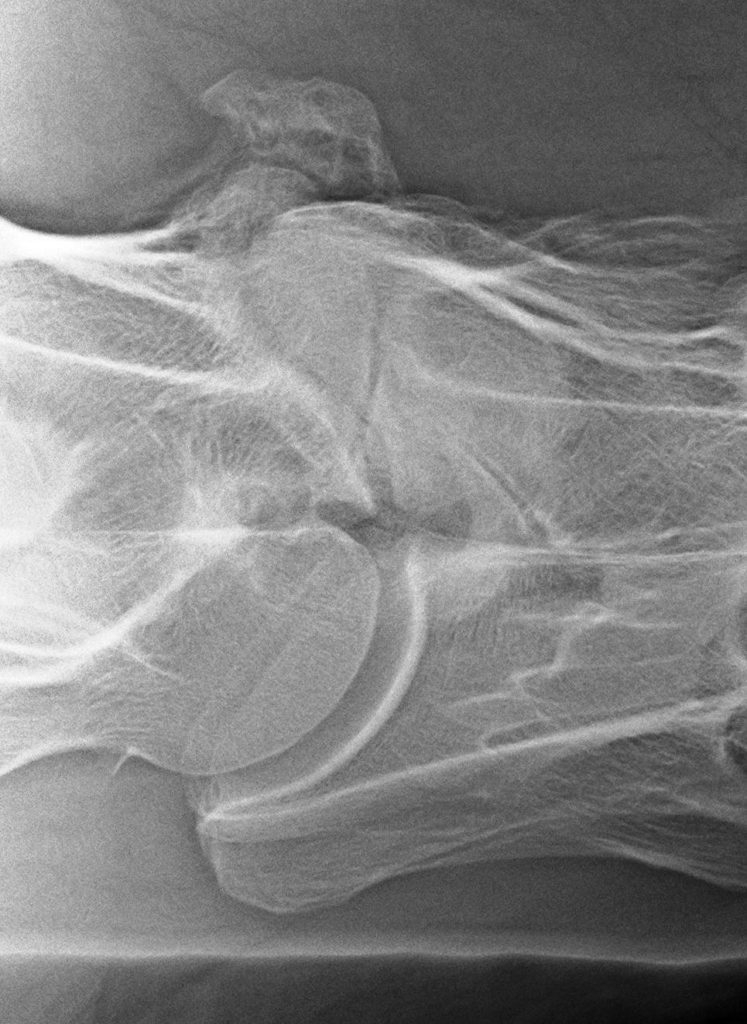

Het klinische onderzoek kunnen we aanvullen met beeldvorming. Op röntgenopnamen kunnen we de facetgewrichten van de gehele hals beoordelen, bij een zijdelingse opname zien we echter beide facetgewrichten over elkaar heen geprojecteerd. Om deze apart te kunnen beoordelen kunnen we “schuine” foto’s maken, ofwel uitprojecties.

Links: Wervellichamen T1-C6

Rechts: Rontgenopnamen T1-C7

Wervellichamen T1-C6

Rontgenopnamen T1-C7